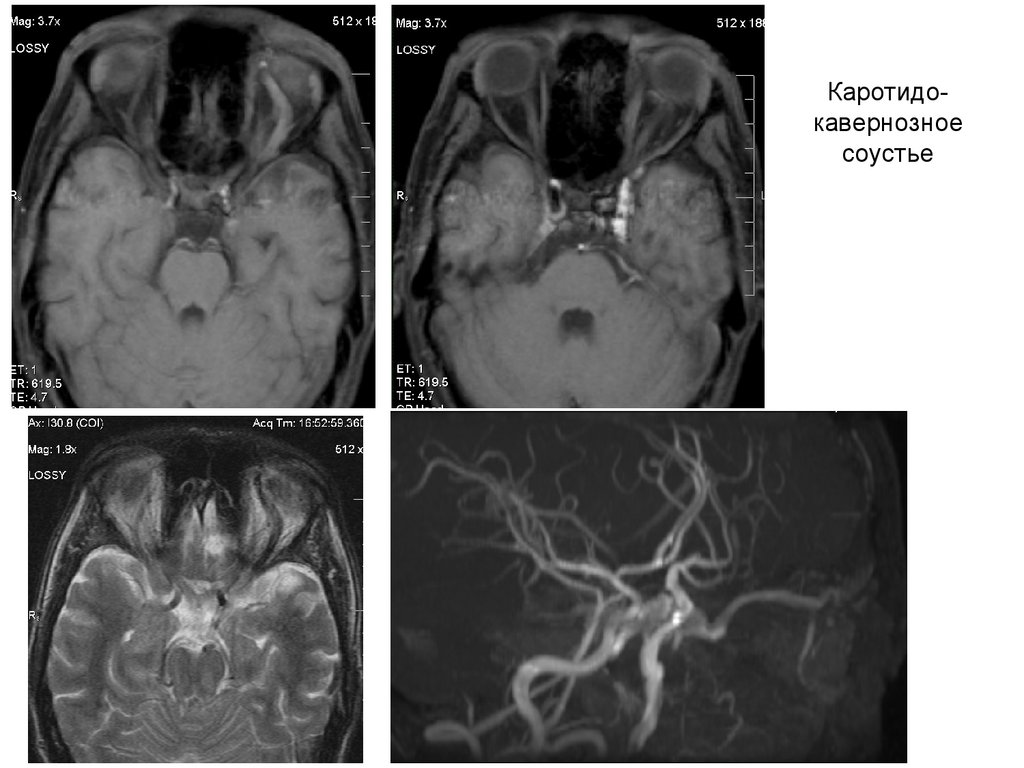

Каротидокавернозное

соустье